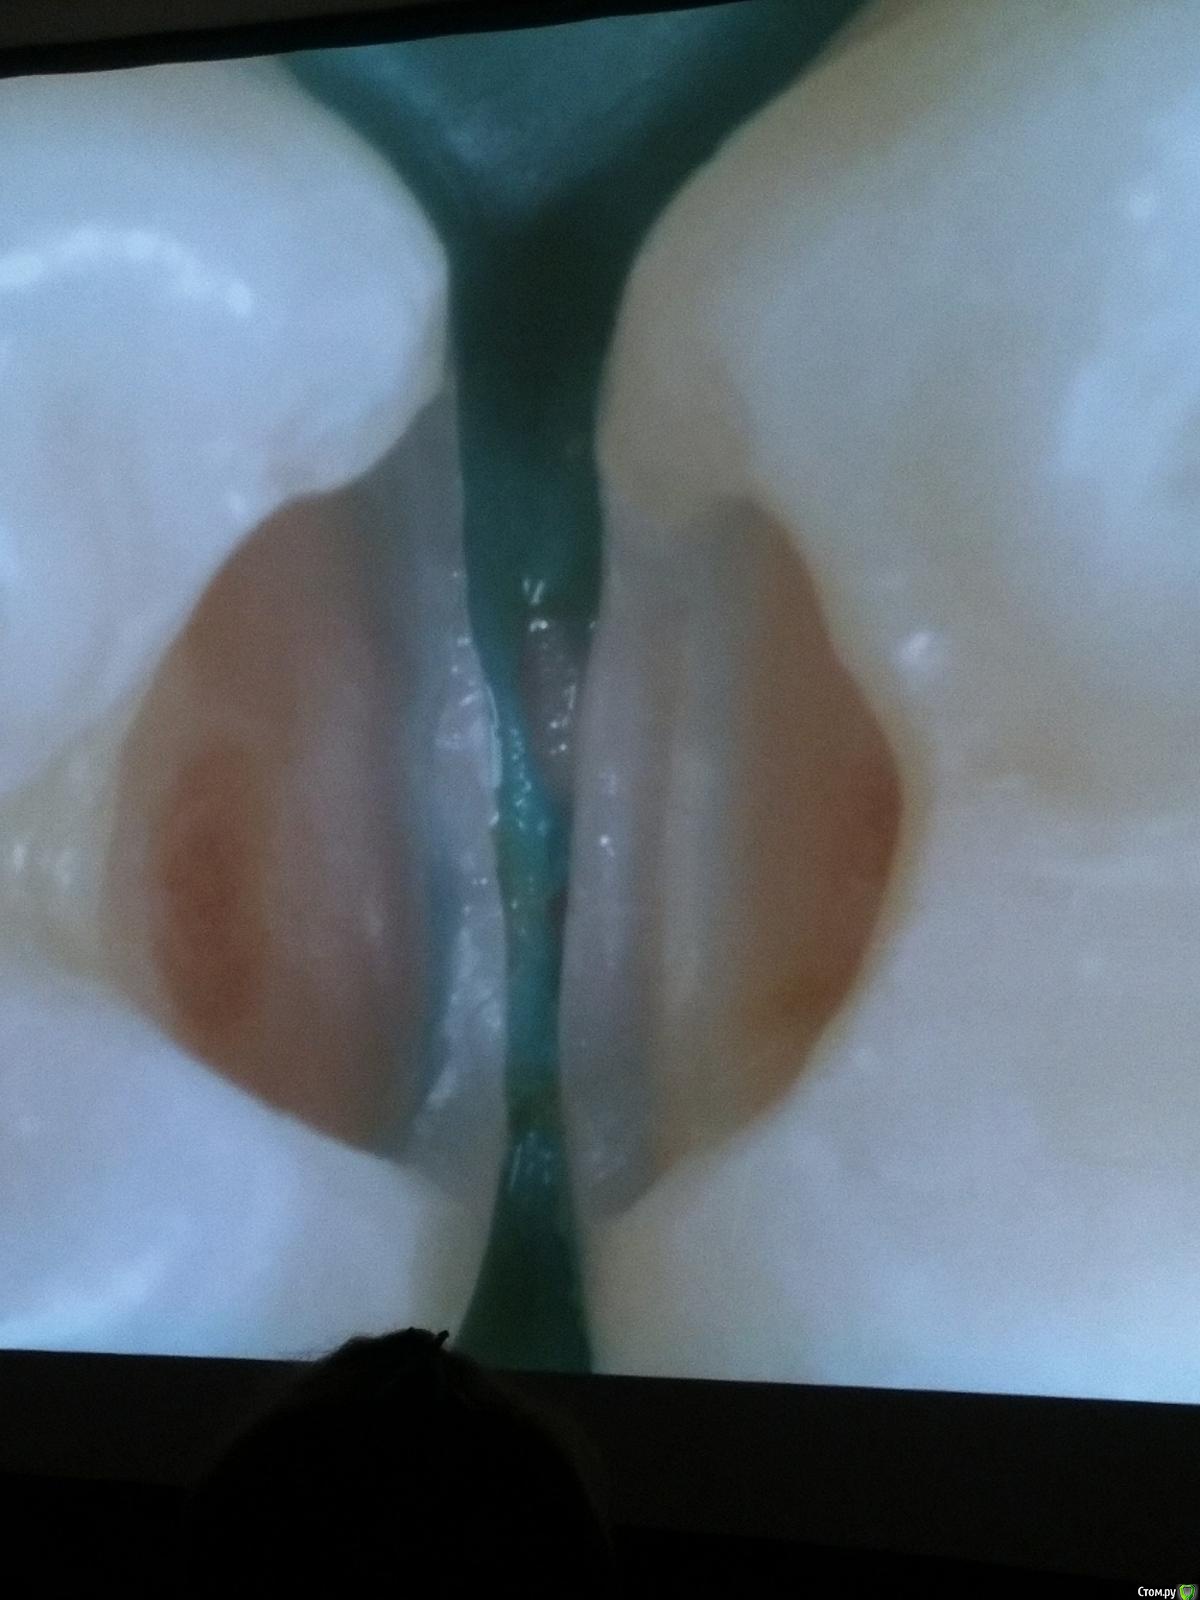

Популярный пост Kolchanov Опубликовано 11 марта, 2017 Популярный пост Поделиться Опубликовано 11 марта, 2017 (изменено) Товарищи, скажу я вам...........Вкратце. Может я где-то что-то и приврал, надеюсь, кто еще был, поправят. Честно говоря немного прибалдел от уровня Доктора. Очень, очень высоко! Приедет еще раз, пойду еще. 1) Фиссуры зондирует острым зондом и выпиливает все дотла. По факту у него уже пломбы, а не герметизация.2) Bite-wing у первичных пациентов всегда.3) Если кариес диагносцирован, то лечить его, пофиг какой он там. Эмали, дентина…4) Препарирует до твердого (или до вскрытия J ). CAD, СID… в топку. Кариес маркером не пользуется, проверяет острым зондом/экскаватором. Вычищает все дотла. Считает, что даже небольшое количество бактерий в дентине под пломбой вызывают хроническое воспаление в пульпе. С его слов у него на контроле где-то 500 вскрытий, не удивительно при таком подходе к очистке.5) Тщательная изоляция. Коффер порвался – меняет. Большое значение герметичности реставрации. под замену6) Критерии обратимости и необратимости.Гистологически, обратимый тот, что без абсцессов в пульпе, но клинически это понять нельзя, только предположить.Здесь был бы обратимый, если бы не удалил. Нет микробов в пульпе. Линия - граница обработки.Покрытие 27 лет назад. Dycal, СИЦ, композит. От дайкала одно воспоминание.7) Вскрылись. Размер перфорации, возраст и прочее не играют роли, важно только состояние пульпы, т.е. диагноз.Примеры перфораций.8) Кровотечение останавливает стерильным ватным шариком. Если останавливается, то покрытие, если нет, то пульпотомия или пульпэктомия.9) Использует гидроокись кальция (порошок), перекрывает Dycal или СИЦ. Потом восстановление Нередко под IRM, потом все убирает (через пару-тройку месяцев) и смотрит, что получилось. Порой приходится повторять! Использует и МТА, его тоже убирает.10) Наблюдение 6мес, 1 год, 2…. Все может провалиться и через месяц и через 24 года.Примеры проваловНиже - 24 года спустя появилась дуля. 11) Неравномерная облитерация полости зуба на RG (после покрытия) – признак текущего хронического воспаления, где-то остались микробы. Рекомендует эндо.12) Мостик который образуется – это не дентин! И одонтобласты не регенерируют и новые не образуются. Что это такое он и сам не знает, но раз это твердые ткани, то и наплевать.Вот фиолетовое это дентинные опилки вмурованные в розовую ткань бог знает кем сформированную.13) Пульпотомия в зубах с несформированной верхушкой и в сформированных, при подозрении на частичное поражение коронковой пульпы. Иссекается стерильным алмазным бором часть пульпы, гидроокись, временная пломба на 90 дней, после повторное раскрытие, оценка результата, восстановление в случае формирования твердых тканей. Гипохлоритом можно мыть, можно не мыть, если мыть, то 0,5-1%.14) В апикальной части пульпа чаще витальна, чем нет.15) Периапикальные поражения возникают по причине поступления токсинов микробов с током крови, а не самих бактерий.16) За апикальные расширения в полностью некротических случаях. Надо механически отодрать биопленку и срезать инфицированный дентин. На ирриганты надежды мало.17) Биопленка на поверхности в 6% случаев.Синенькие пид@расы18) Обработку проводить нежно, краун-даун. Чередовать с H-файлом, чтобы посмотреть докуда распространяется некроз.19) Патенси в витальных кейсах не колоть, сохранять витальную пульпу в констрикции!Формирование еще большего сужения в констрикции за счет сохранения витальной пульпы. Изменено 11 марта, 2017 пользователем Kolchanov 31 Ссылка на комментарий

Популярный пост Kolchanov Опубликовано 12 марта, 2017 Автор Популярный пост Поделиться Опубликовано 12 марта, 2017 Второй день.1) Дезинфекция зуба и раббер дама перед работой. Вначале установка системы, потом протирка тампоном 30% перекиси, потом протирка всего йодинолом. Потом преп, потом повторение и только потом доступ к к/к. Все старые реставрации надо убрать, кариес убрать, противник лечения через коронку.2) Гидроокись на неделю. Замешивает на стерильном физрастворе. При необходимости повторяет. Т.е. в случае сохранения свища, симптоматики, экссудации, запаха. Если свищ не исчезает после трех смен временных вложений, то хирургия.3) Пломбирует латеральной компакцией. Лучше контроль длины обтурации.4) Высушивание канала стерильными штифтами, на рабочую длину минус 1мм. После высушивания штифт оставляется на 60с. в канале и должен выйти сухим.5) Определение рабочей длины. Витальные случаи. АЛ должен три раза дать одну и ту же картинку в определенной точке + проверка RG. Девитальные случаи. На АЛ полагаться сложно, т.к. из-за наличия резорбции констрикции может врать, больше ориентируется на RG.6) Использует ЦОЭ силеры. Резорбируются при незначительном выведении. Резорбируются в канале, позволяя закрыть апекс цементоподобной тканью. Вот так вот.Случаи исчезновения силера, как за пределами канала так и в канале7) Выведение материала (не важно какого) в большом объеме способно вызвать защитную реакцию тканей. Которая должна пройти спустя некоторое время. (иногда это будет 25 лет J Случай 1ый. Студенты наломали инструментов. Периодонтит на RG через год. Резекция и гистология. Бактерий не обнаружил. Да, маленькое замечание. Каждый препарат дает 500-600 срезов. И ищет он на всех. Объем работы, конечно….Случай 2й. Его собственный. Периапикальное поражение, обнаруженное на реколле через 10 лет зажило еще через 15.8) «Функционирующий зуб» считает результатом неприемлемым. Осталась инфекция с которой надо что-то делать. То, что бактерий можно замуровать в дентинных трубочках и под пломбировочным материалом, считает неправильным. Продукты метаболизма один фиг будут просачиваться и могут поддерживать реакцию воспалительную.Случай. Синее – маленькая кучка микробов, предположительно, препятствовавших заживлению очага.9) Биопленка на поверхности корня может принимать вид кальцификатов (камней) и тут уже только хирургия в помощь. При длительном существовании свищевого хода, например.Черное - это камни вокруг апикального отверстия. И гистология их с кучей синих микробов.Здесь камни на фуркации и отсутствие заживления и свищ даже после ретроградной обработки и пломбировки.А здесь вообще чертова уйма камней. И зацените разветвление канала в этом боковом резце (последнее фото препарата). 10) Реваскуляризация.В некротических случаях дентина не образуется, т.к. одонтобластов нет и не будет новых. Образуется та самая бог знает какая ткань, которая даже и с корнем не связана может быть. Суть здоровый дентикль-петрификат. А в витальных это не реваскуляризация, а обычное формирование корня. Так что нечего тут.11) Трещины дентина.Советует расшивать, братья и сестры. Без фанатизма, если нет симптоматики, но, по возможности максимально. Если есть симптоматика, то там уже по обстоятельствам. Чертова уйма микробов там и ползет, ползет к пульпе. Надеюсь, что еще раз этот замечательный Доктор приедет. Схожу с удовольствием. 2 23 Ссылка на комментарий